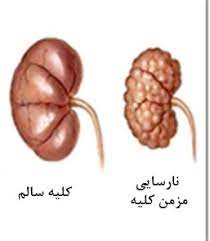

قیمت: 32٬000 تومان - دسته بندی فایل: علوم پزشکیپاورپوینت نارسایی مزمن کلیه

فروش ویژه پاورپوینت حرفه ای نارسایی مزمن کلیه با تخفیف استثنایی فقط 62453 هزار تومان تعداد اسلاید : 27 اسلاید